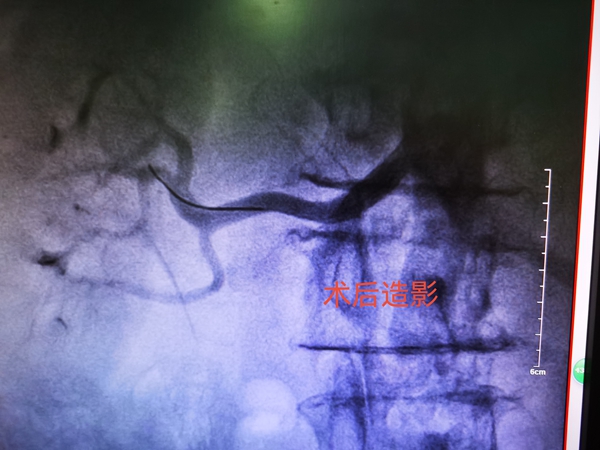

經(jīng)院委會成員、心血管內(nèi)科專家李國,心血管內(nèi)科主任曹志偉,介入科主任張凌志會診后,給予患者經(jīng)橈動脈行右側腎動脈球囊擴張、支架植入術,術后患者未訴不適,血壓將至150/70mmHg左右。